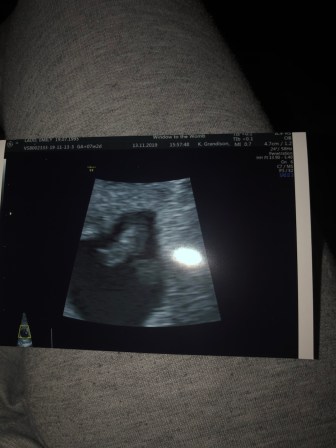

We went to our early scan today at Window to the womb in Southampton. We paid £49 as they had a offer on at the time. So excited!!

I was scanning at 6w 6d. It was such a relief to see the little bean on the screen. The first thing the lady said was that the heartbeat was very strong and we could see it flickering away. She also said I ovulated from my left ovary, no blood around the sac or the baby. Which was a huge relief for me. When we got home I still was super nervous to see blood when I wiped but I rang the GP and made a midwife appointment even though it was going to take 3 weeks to see one.

Today was the day we got to see baby Ladd on the screen! We managed to get to the screen on time even though it was tipping it down with rain and we decided to walk up. Phoebe was good as gold as per watched Peppa on her amazon fire kindle we tried to point at her brother/sister but she had no idea. Once again strong heartbeat and a wriggler just like its sister was. We were in there scan room for over half an our due to the little bean wriggling around trying to get measurements. I was reading at 12w 6days which is what I thought roughly. Everything seamed fine and normal which was great we got some good scan photos this baby is the opposite side to what Phoebe was.